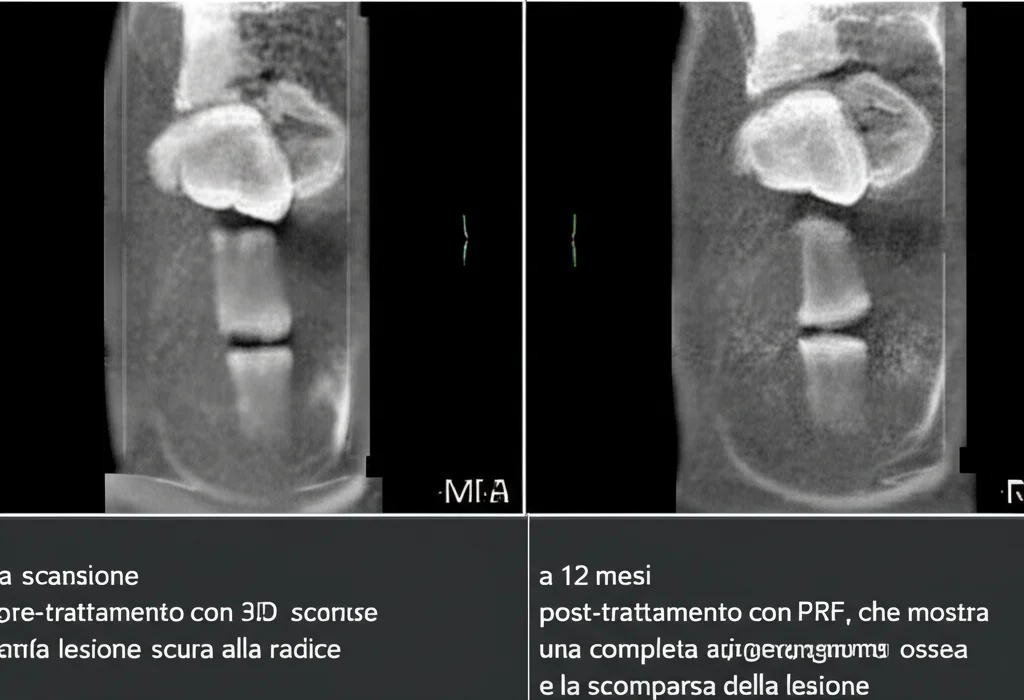

Per valutare i risultati in modo super preciso, i ricercatori non si sono accontentati delle tradizionali radiografie periapicali (le piccole lastrine bidimensionali), ma hanno usato la Tomografia Computerizzata Cone Beam (CBCT). La CBCT è fantastica perché ci dà immagini tridimensionali e permette di misurare il volume esatto delle lesioni, superando i limiti delle radiografie 2D dove le strutture si sovrappongono. Hanno misurato il diametro massimo e il volume delle lesioni all’inizio dello studio e dopo 12 mesi. Inoltre, hanno verificato se i denti trattati rispondevano ai test di sensibilità termica (freddo) ed elettrica, un indizio importante sulla possibile rigenerazione di tessuto vitale.

Innanzitutto, la buona notizia è che entrambe le tecniche hanno funzionato molto bene nel ridurre le dimensioni delle lesioni periapicali. Utilizzando la CBCT, si è visto che:

- Nel gruppo trattato con Coagulo Sanguigno (BC), il volume medio della lesione è passato da 0.33 cm³ a 0.13 cm³. Una riduzione notevole! L’85% dei denti ha mostrato una riduzione della lesione.

- Nel gruppo trattato con Fibrina Ricca di Piastrine (PRF), il volume medio è sceso da 0.27 cm³ a un incredibile 0.04 cm³! Qui, il 100% dei denti ha mostrato una riduzione della lesione.

Statisticamente, però, la differenza nella riduzione del volume tra i due gruppi non è stata considerata significativa. Questo significa che, dal punto di vista della guarigione ossea visibile radiograficamente, entrambe le tecniche si sono dimostrate efficaci e comparabili in questo studio su denti maturi ritrattati.